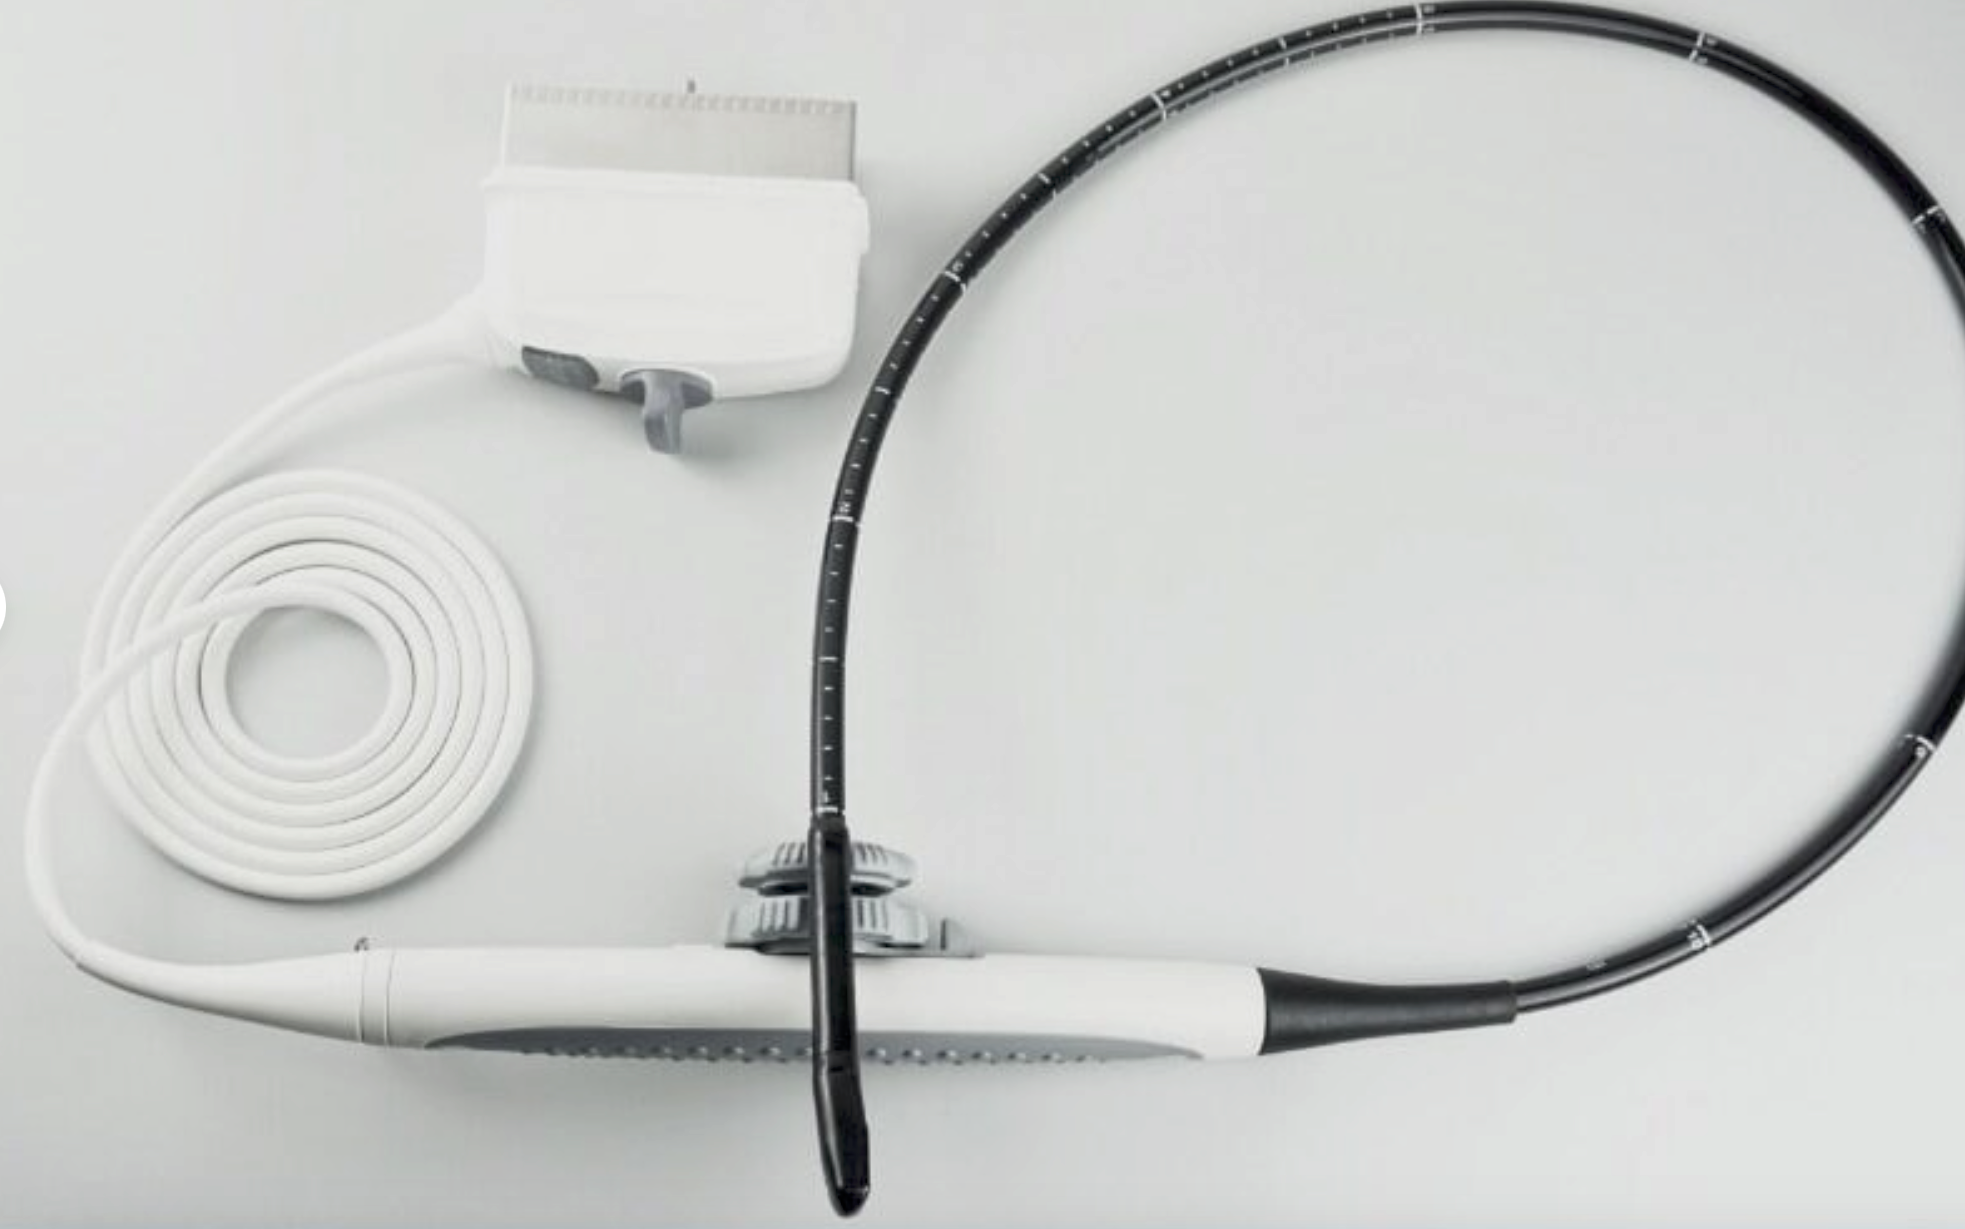

Wireless Fetal Doppler Convex Probe Veterinary Ultrasound for iPad, iPhone App

Wireless Wifi Doppler Convex Array Probe Type Ultrasound Scanner. This wireless Wifi Convex Array Probe with integrated ultrasound circuit boards inside, then realize the functions of an ultrasound scanner. It can be used at many occasions such as In emergency, clinical, and hospital. In addition, CT is easy to operate because it has a unique design with three buttons which is a portable ultrasound machine.

- Integrated ultrasound circuit board inside

- Connect wirelessly wifi to Tablet or Smart Phone

- Downloadable APP gives functions of the ultrasound scanner

- Built-in Replaceable Battery, 3 hours working time, 5 hours standby